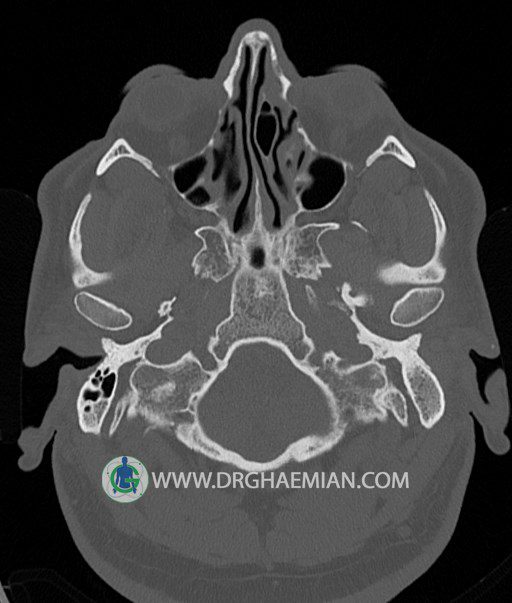

سی تی اسکن گوش داخلی به رادیولوژیست اجازه می دهد تا سطوح مختلف، یا اسلایس هایی از استخوان های که از جمجه به گوش می روند را از طریق امواج ایکس چرخشی مشاهده کند. در این کیس اودیت مدیا، ماستوئیدیت مزمن، اوتیت خارجی، انحراف سپتوم بینی، کونکا بولوزا و افزایش ضخامت سینوس ها مشاهده می شود.

در HRCT از استخوان تمپورال با مقاطع آگزيال ، ساژيتال و کرونال ظريف ( 0.6 mm ) :

– اپاسيتي گوش مياني چپ ناشي از وجود دانسيته نسج نرمي دراطراف استخوانچه ها همراه با اروژن اسکوتوم و

استخوانچه ها بدون جابجايي در رديف استخوانچه ها مشهود است که مطرح کننده اوتيت مديا همراه با نشانه

هاي مشکوک به کولستئاتوم مي باشد .

– اپاسيتي و اسکلروزيس ماستوئيد چپ نشانه ماستوئيديت مزمن

– اپاسيتي کانال گوش خارجي ناشي از دانسيتي نسج نرمي مطرح کننده external otitis